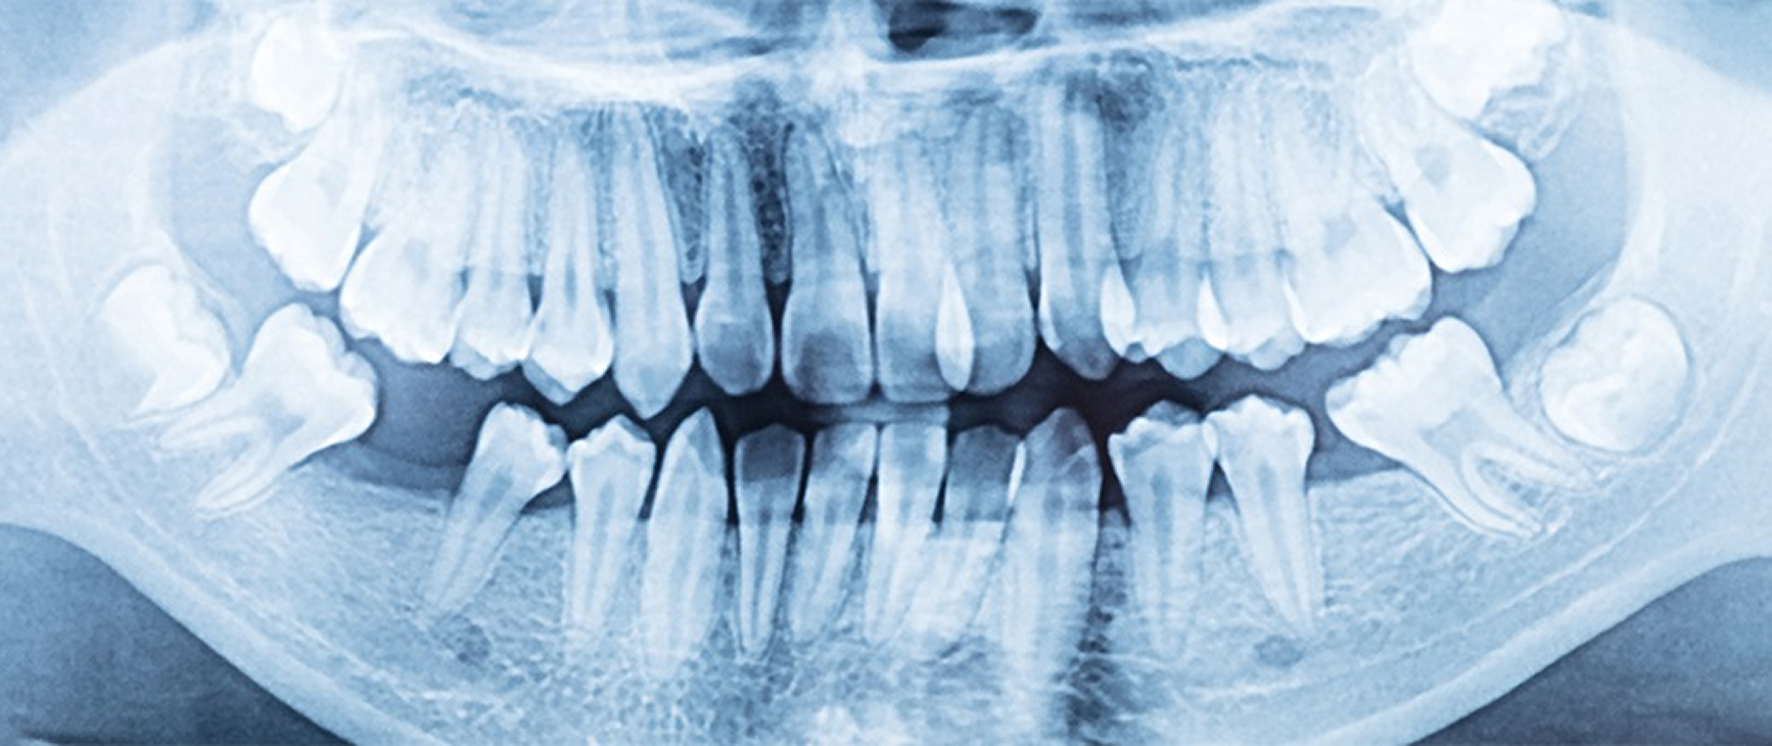

Цифровой ортопантомограф — точные снимки всей полости рта за секунды и надёжный помощник врача для быстрой и безопасной диагностики.

Цифровой ортопантомограф позволяет нам существенно экономить время, за счет обеспечения быстрых и высококачественных изображений. Процедура панорамного снимка не несет никакого вреда для здоровья человека, так как дозы излучения крайне малы.

Снимки ортопантомографа регистрирует специальный датчик, который обладает высокой чувствительностью к рентгеновским лучам. Готовый снимок распечатывается на бумагу (в случае необходимости).

Панорамный снимок предоставляет врачу получать снимки зубов, челюстных суставов и гайморовых пазух, а также снимки всего зубного ряда у маленьких и взрослых пациентов.